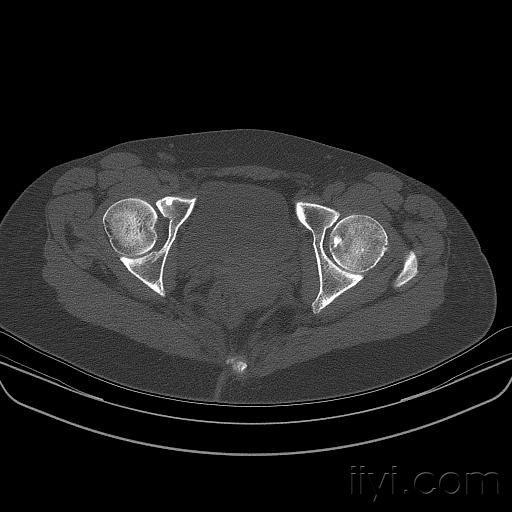

各位大师请判断,骨岛?骨纤?转移瘤?如何进行下一步?